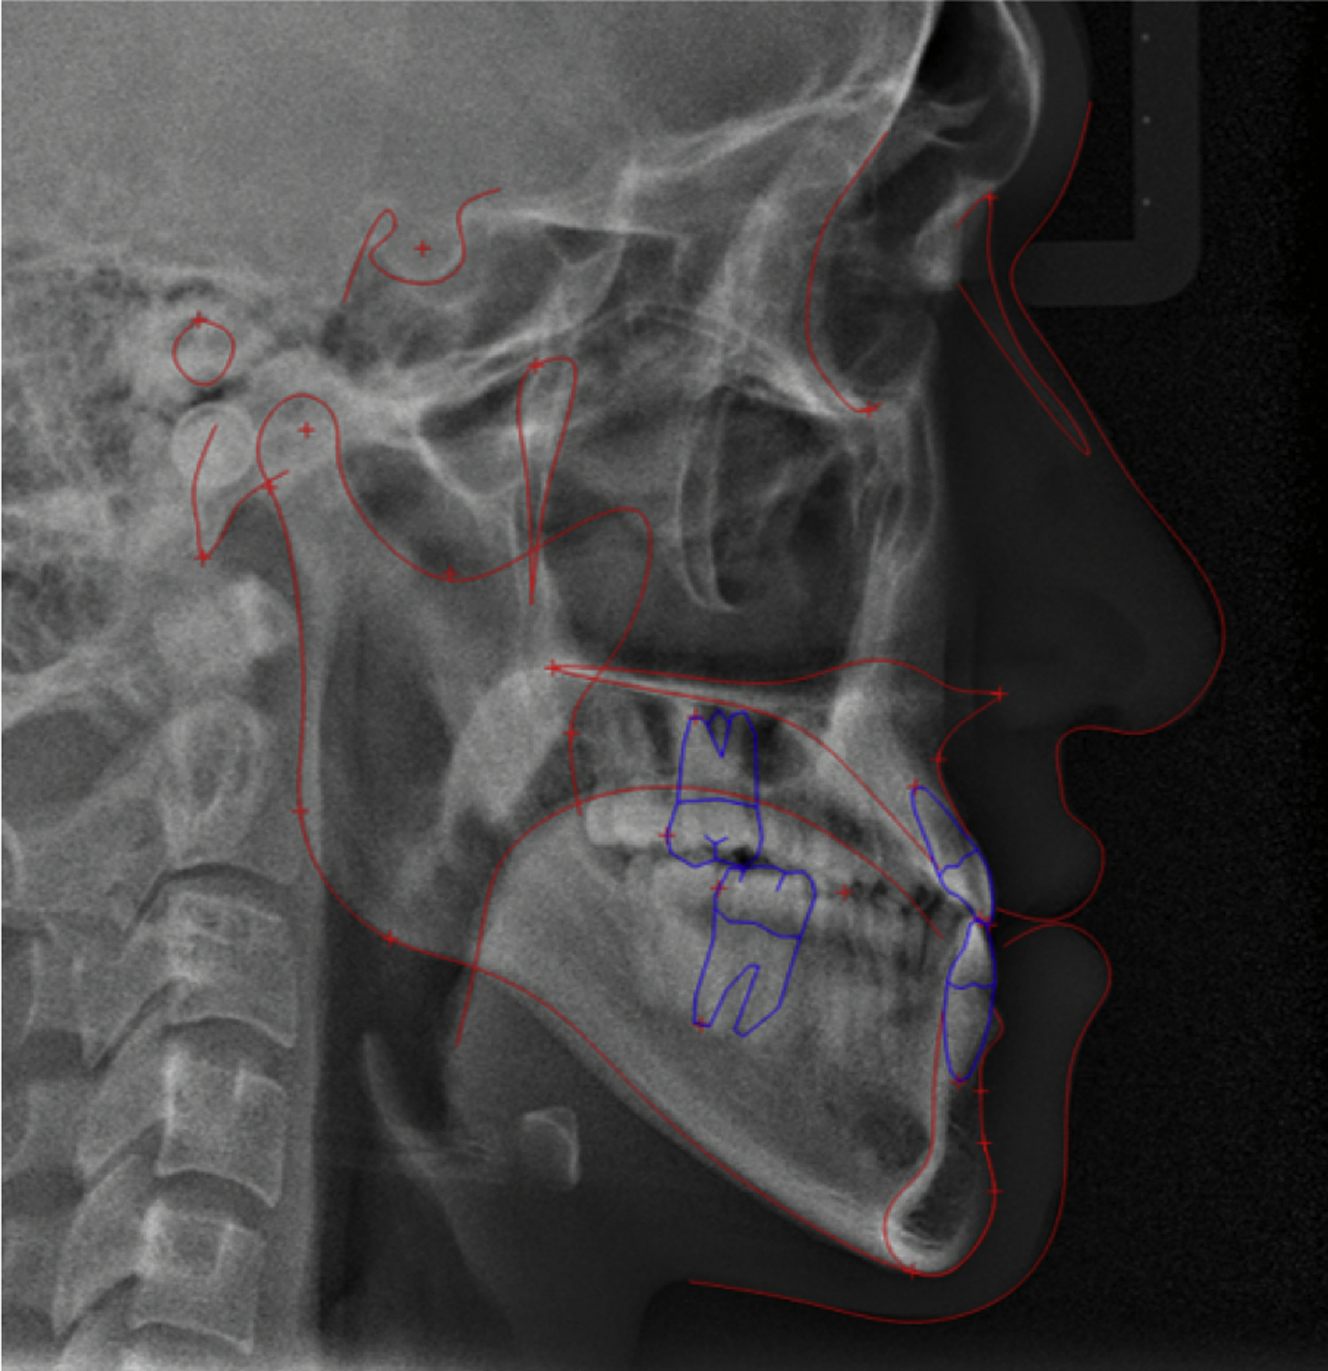

The lateral cephalometric analysis revealed a class III skeletal pattern with an point A-nasion-point B angle of −2.7°, and Wits appraisal of −7.7 mm. mandibular plane angle (angle between sella-nasion and gonion-gnathion) was 42.7°, indicating a long face. The upper incisors were proclined with a upper incisor inclination (U1-FH) of 132.4°. The lower incisor inclination was 92.4°, measured relative to the mandibular plane ( Fig. 4 , Table 2 ).

Before the surgery, usually presurgical orthodontics is performed. As the teeth are often compensated to the patients’ skeletal pattern, a process of decompensation is done to accommodate the postsurgical occlusion. In the case of class III malocclusion, upper and lower incisors often exhibit proclination and retroclination, respectively, to compensate for the skeletal discrepancy ( Fig. 6 ). In patients who have severe crowding with upper incisor protrusion, the upper bicuspids could be extracted to relieve crowding and retract the incisors. Lately, the surgery-first approach (SFA) has increased because of advantages, such as the immediate improvement of facial esthetics, patients’ psychosocial status, shorter treatment time, and physiologic tooth movement. Despite the advantages of the SFA, care should be taken owing to the unstable occlusion after surgery. There are greater vertical and sagittal changes in the occlusion during postsurgical orthodontics, making it less predictable for the final skeletal relationship. In addition, premature contact in the postsurgical occlusion might lead to surgical relapse, and possibly to TMD because of condylar displacement. Therefore, to obtain predictable results in the SFA, accurate diagnosis and treatment planning, accurate laboratory procedures, and much clinical experience are required.

Patients expect an esthetic outcome in addition to the correction of their malocclusion. Therefore, the treatment plan should be based on a careful assessment of the facial soft tissues in addition to analyzing the skeletal and dental anomalies. Arnett and colleagues suggested 7 steps for OGS planning using lateral cephalograms, as follows ( Fig. 7 ):

- 1.

Correct the torque of the maxillary incisors (see Fig. 7 A and B).

The patient had proclined upper incisors; therefore, the upper incisor torque was corrected.

- 2.

Correct the torque of the mandibular incisors.

The patient had lower incisor torque within normal ranges; therefore, no changes in the lower incisors were planned.

- 3.

Position the maxillary incisor (Le Fort I).

The maxilla was moved up and forward (see Fig. 7 C).

- 4.

Autorotate the mandible to 3 mm of overbite.

After maxillary repositioning, the mandible was autorotated to occlude with the upper teeth (see Fig. 7 D).

- 5.

Move the mandible to 3 mm of overjet.

The mandible was set back to obtain a normal incisor overjet (see Fig. 7 E).

- 6.

Set the maxillary occlusal plane.

The patient had a flat occlusal plane; therefore, posterior impaction was performed, resulting in the clockwise rotation of the maxillomandibular complex. This resolves the mandibular protrusion (see Fig. 7 F).

- 7.

Assess chin projection and height.

The patient shows normal chin projection with an improved facial profile.